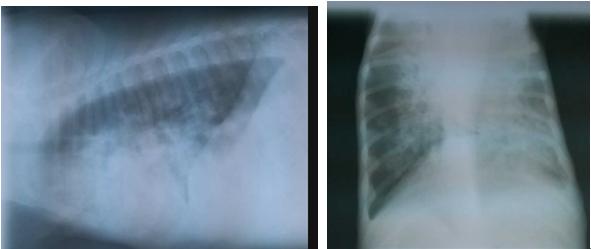

2.2.3 影像学检查

X线可见,心脏影像模糊,消失,肺野阴影加深,支气管纹理及血管纹理加深,肺野大面积散状结节影像,提示肺水肿,肺实变。

5.2 突然发病,高度混合型呼吸困难,患犬湿咳,头颈伸展,张口呼吸,鼻翼扇动,两鼻孔流出白色泡沫样鼻液为该病典型的临床症状,依据X线检查可以确诊;